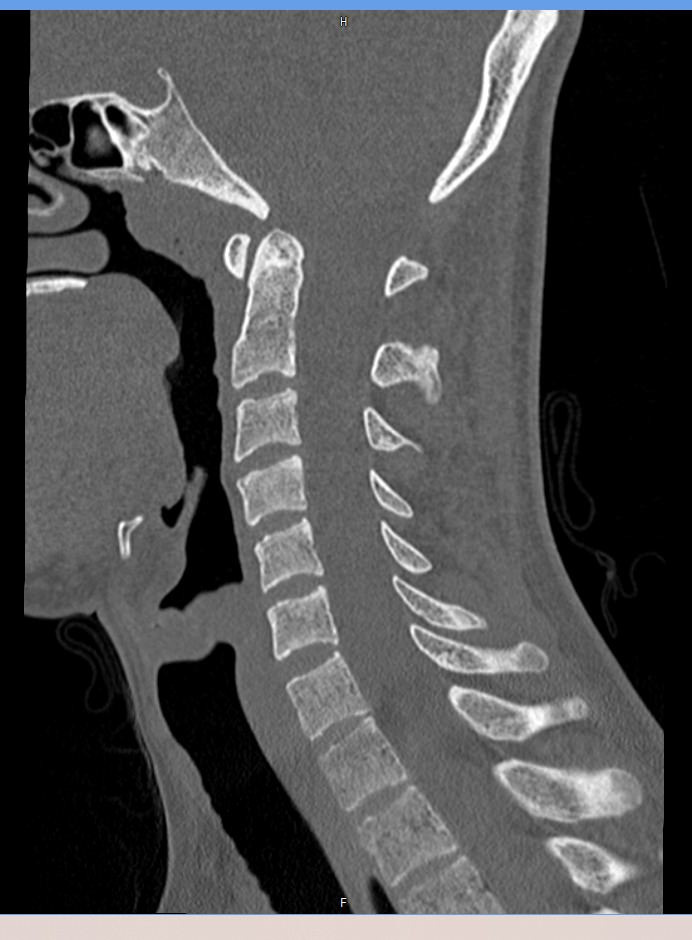

На снимках КТ хорошо визуализируются позвоночные суставы, суставные поверхности, межпозвонковые диски, которые часто подвержены дегенеративно-дистрофическим процессам. На томограммах также можно оценить состояние позвоночного канала, в котором располагается спинной мозг, выявить участки его сужения и предположить степень воздействия на спинномозговые структуры.

При обследовании шейного отдела позвоночника оценивается область основания черепа, семь шейных позвонков, верхние грудные позвонки. Помимо костных структур мультиспиральная КТ показывает состояние близлежащих органов и тканей: трахеи, пищевода, лимфатических узлов, кровеносных сосудов на исследуемом уровне.